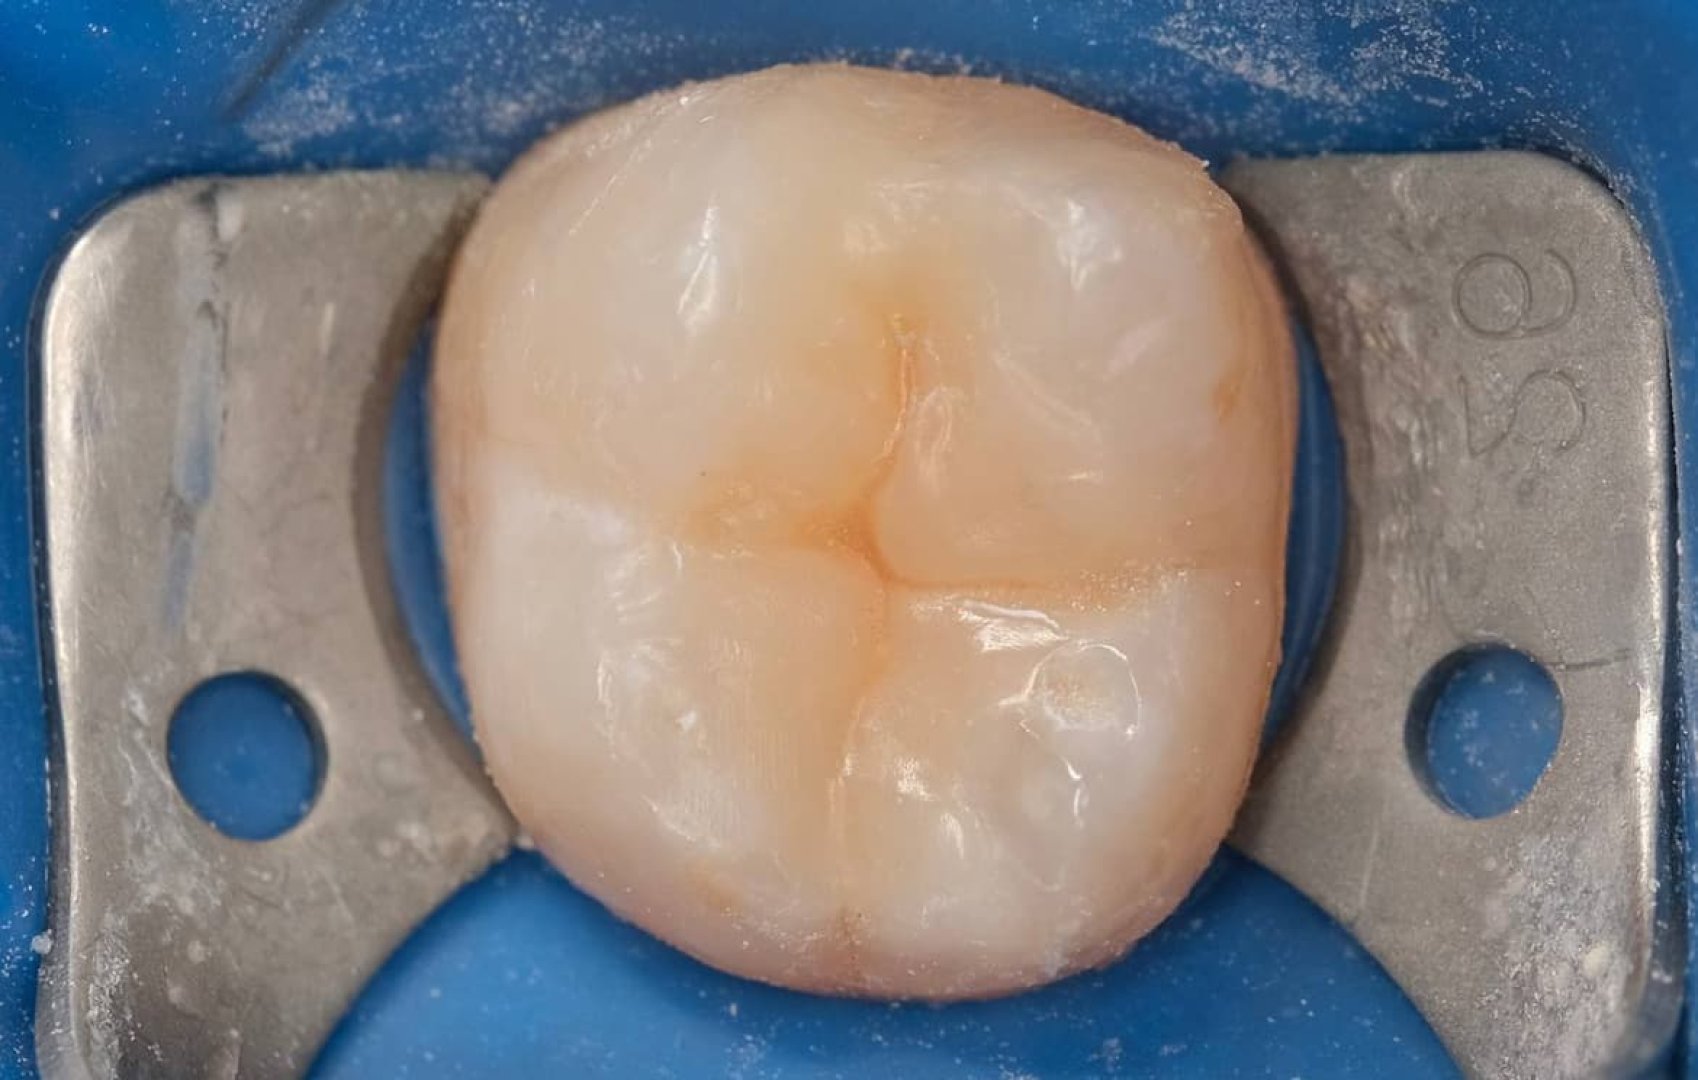

Замена старой пломбы 4.7

Пациент обратился со старой пломбой, установленной на изолирующую прокладку. Такие конструкции со временем становятся уязвимыми.